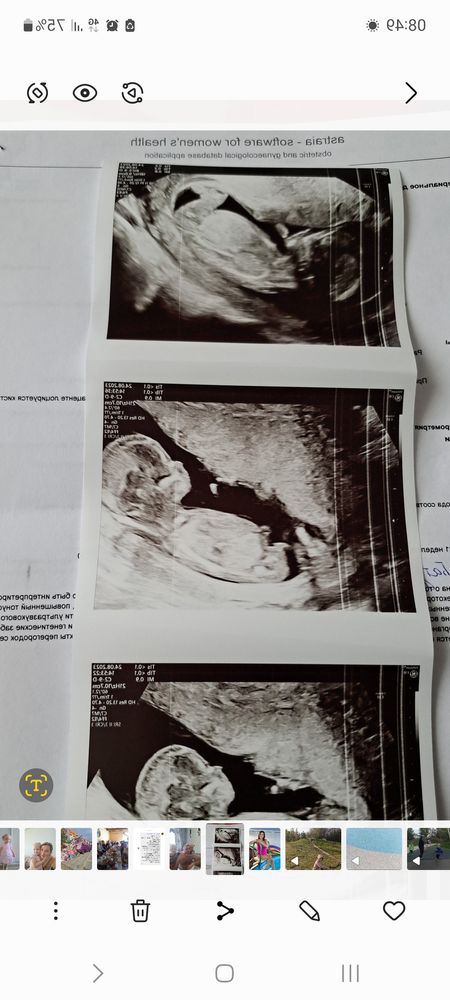

Татьяна, есть, последняя на телефоне, а те две нужно искать, но они идентичны)

Мальчик 100% у меня девочка, положение вообще другое) при чем трижды)))